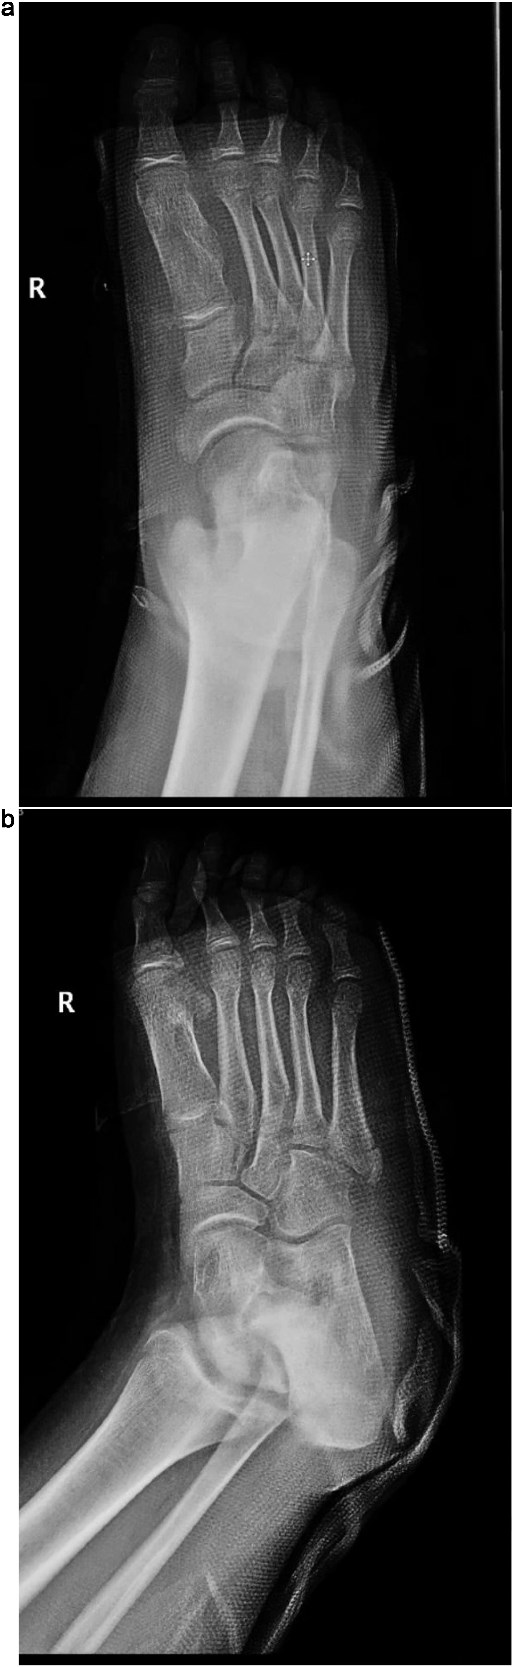

Plain radiographs revealed a bony mass extending from the medial cuneiform to the first metatarsal, with the first and second intermetatarsal space widening (Fig. 1). Magnetic resonance imaging (MRI) was performed to better characterize the mass (Fig. 2). Musculoskeletal radiologists reported the presence of an abnormal rudimentary bone that was interposed between the first and second metatarsal bones, with pseudo-articulation and ankylosis with the lateral aspect of the mid-metatarsal shaft of the hallux, causing widening and deformity, suggesting a supernumerary rudimentary metatarsal bone. An osteochondroma was also considered in the differential diagnosis, but the cartilage cap was not clearly visible. As daily activities were significantly affected, the patient’s guardian preferred surgical excision over more conservative measures, which had previously been unsuccessful.

(a) Lateral radiograph of the right foot demonstrating a bony mass extending from the medial cuneiform to the first metatarsal. (b) Oblique radiograph of the right foot highlighting the abnormal bony outgrowth between the first and second metatarsals. (c) Anteroposterior radiograph showing a bony mass arising from the medial cuneiform extending toward the first metatarsal, with widening of the first intermetatarsal space.